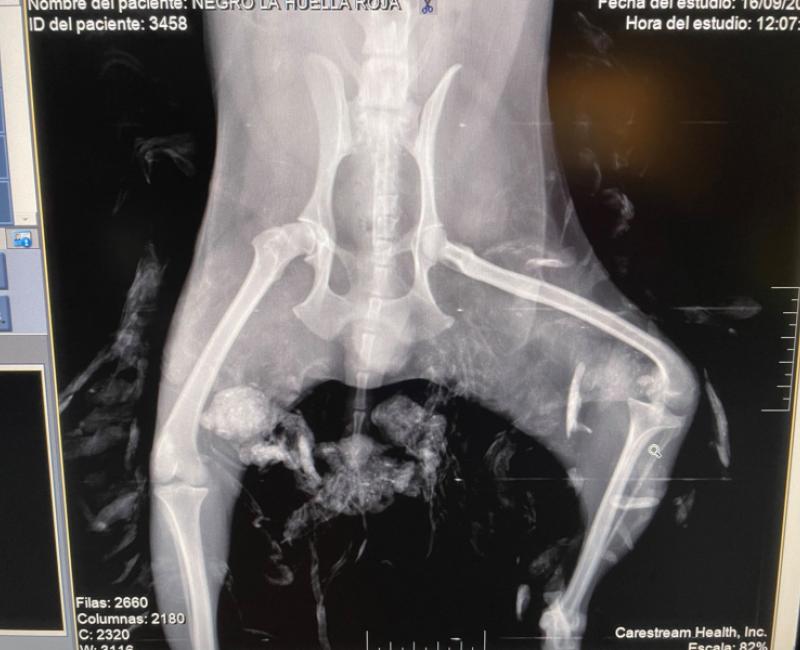

Ya ha sido revisado por la veterinaria. Tiene una pata deformada a consecuencia de algún golpe. Por ahora no tiene dolor así que ahora mismo no se le va a realizar la amputacion, que realmente es la única solución.